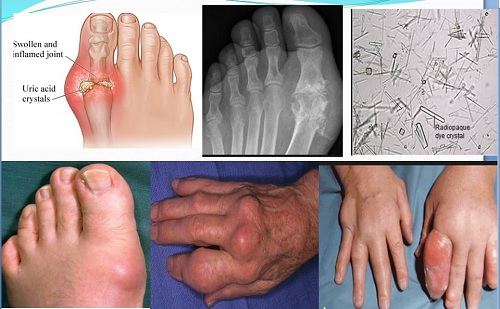

Bất ngờ đầu tiên thuộc về nghiên cứu chuyên sâu của trường ĐH Y Dược Huế vào năm 2002 với đề tài “Sưu tầm, định danh, xác định thành phần hóa học và tính chất sinh học một số cây thuốc của dân tộc bản địa tỉnh Đắk-Lắk”. Sau khi nghiên cứu về cây Tơm trơng, gần 30 nhà khoa học và cán bộ của trường ĐH Y Dược Huế đã đưa ra công bố: Thành phần Phytosterol trong cây Tơm trơng có tác dụng ức chế sinh tổng hợp axít uric, bổ thận tráng dương, tăng cường chức năng đào thải axít uric ra bên ngoài đồng thời duy trì sự ổn định và giúp cơ thể người bệnh gút trở lại cân bằng.

Chưa hết, hoạt chất Phytosterol còn có tác dụng chống viêm hữu hiệu. Qua đó giúp giảm sưng đau, giảm viêm trong điều trị bệnh gút và các bệnh đau nhức xương khớp khác. Ngoài ra, Phytosterol còn có khả năng điều hòa lipid máu, hạ cholesterol trong máu, chống ô xy hóa, chống nấm, ngăn ngừa xơ vữa động mạch, giảm nguy cơ tai biến, các bệnh về tim mạch, phòng ngừa ung thư…